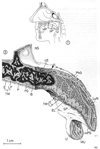

消化器;消化器系【しょうかきけい】(栄養分を取りこむ器官系で、言い換えれば、身体の成長に必要な物質と身体の活動を支えるためのエネルギー源とを取り入れるのが消化器の役割である。消化器は口腔・咽頭・食道・胃・小腸・大腸などから構成された「消化管」とこれに開く唾液腺・肝臓・膵臓などの「消化腺」とから出来ている。)